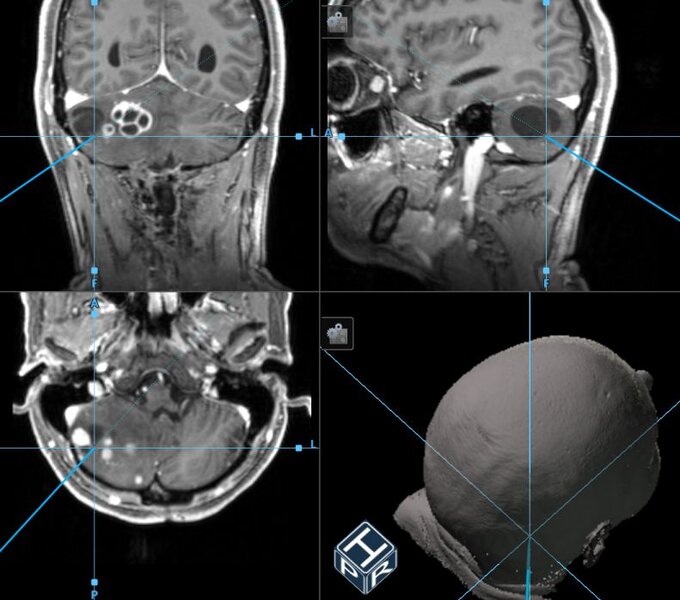

Intraoperative Neuronavigation:

Unter Verwendung der intraoperativen Neuronavigation kann jeder beliebige Punkt hochpräzise im 3D MRT-Datensatz lokalisiert werden. Die Neuronavigation ist somit sowohl für die Planung des operativen Zugangsweges als auch für die gezielte Lagebestimmung von Hämangioblastomen oder deren Zysten von Vorteil.